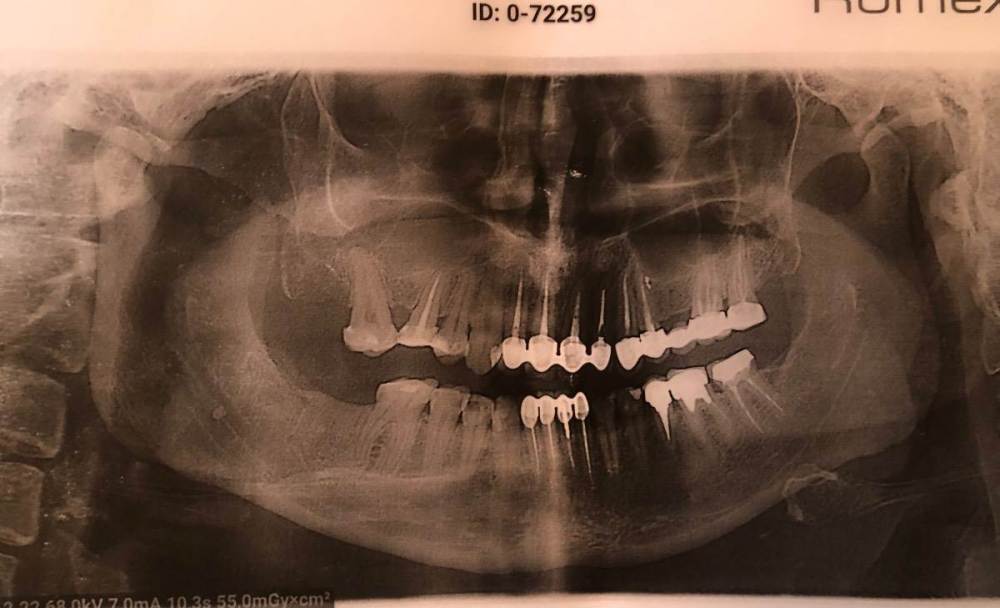

Vasilina24 Опубликовано 9 января, 2023 Поделиться Опубликовано 9 января, 2023 (изменено) Добрый день, уважаемые доктора. Помогите найти выход из ситуации: по заключению кт пазух (делала всвязи с гнойным гайморитом) обнаружена киста справа (5 зуб верхняя челюсть) сообщающаяся с полостью верхнечелюстной пазухи. Парадентальная киста слева. Общее заключение кт выглядит так : МСКТ-признаки реактивных изменений слизистой оболочки клиновидной и левой лобной пазух; правостороннего фронтита, этмоидита, правостороннего гайморита; гиперденсивного компонента по ходу перегородки в решетчатом лабиринте (остеома?); парадентальной кисты справа сообщающейся с полость верхнечелюстной пазухи; парадентальной кисты слева. РЕКОМ ЕНДАЦИИ Консультация оториноларинголога, стоматолога На сегодняшний день была : 1. оториноларинголог : заключение не могу прочесть , написал от руки, но разобрала, что синусит и отправлена к стоматологу. 2. Хирург в стоматологии отправил в челюстно-лицевую хирургию. 3. челюстно-лицевой хирург отправил без записей к стоматологу лечить кисту. Вопрос: насколько целесообразно бороться за зуб? Возможен ли рецидив, уже после лечения кисты? Лечить или удалять? Я уже 1,5 месяца хожу с гноем в носу , стекающим в горло. Ищу врача и все меня отправляют друг к другу. К сожалению пока не могу добавить снимки кт, они на диске, а я не имею доступа к компьютеру. Изменено 9 января, 2023 пользователем Vasilina24 Фото Ссылка на комментарий

red_butler Опубликовано 9 января, 2023 Поделиться Опубликовано 9 января, 2023 Здравствуйте, по приложенному снимку ответить не получиться. Ждем Кт Ссылка на комментарий